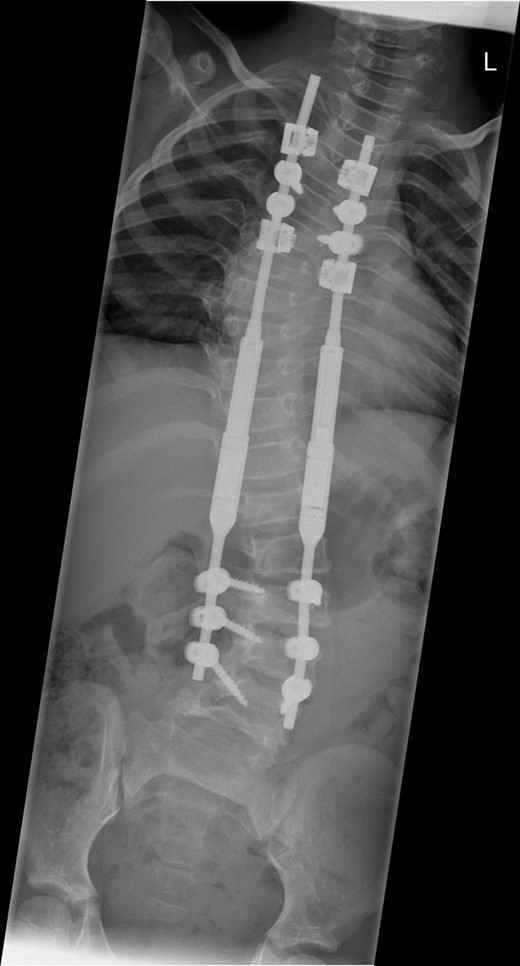

Subsequent transcutaneous, magnetic spinal lengthening has been performed on six occasions in the outpatient setting over the last 2 years. This has been uncomplicated and has not been associated with significant pain or fracture. She takes paracetamol after each magnetic lengthening procedure, easing mild muscular discomfort. The control of the scoliosis has been maintained, and at 2 years post-insertion of MCGR the spinal curves now measure 40° for the thoracic curve and 37° for the thoracolumbar curve with a T1–S1 height of 288 mm and T1–T12 height of 195 mm (Fig. 3). The MCGR have been lengthened by 16 mm on either side.

A whole spine radiograph at age 8 following multiple lengthening procedures showing elongation of the MCGR rods (measuring 40° for the thoracic curve and 37° for the thoracolumbar curve with a T1–S1 height of 288 mm and T1–T12 height of 195 mm).